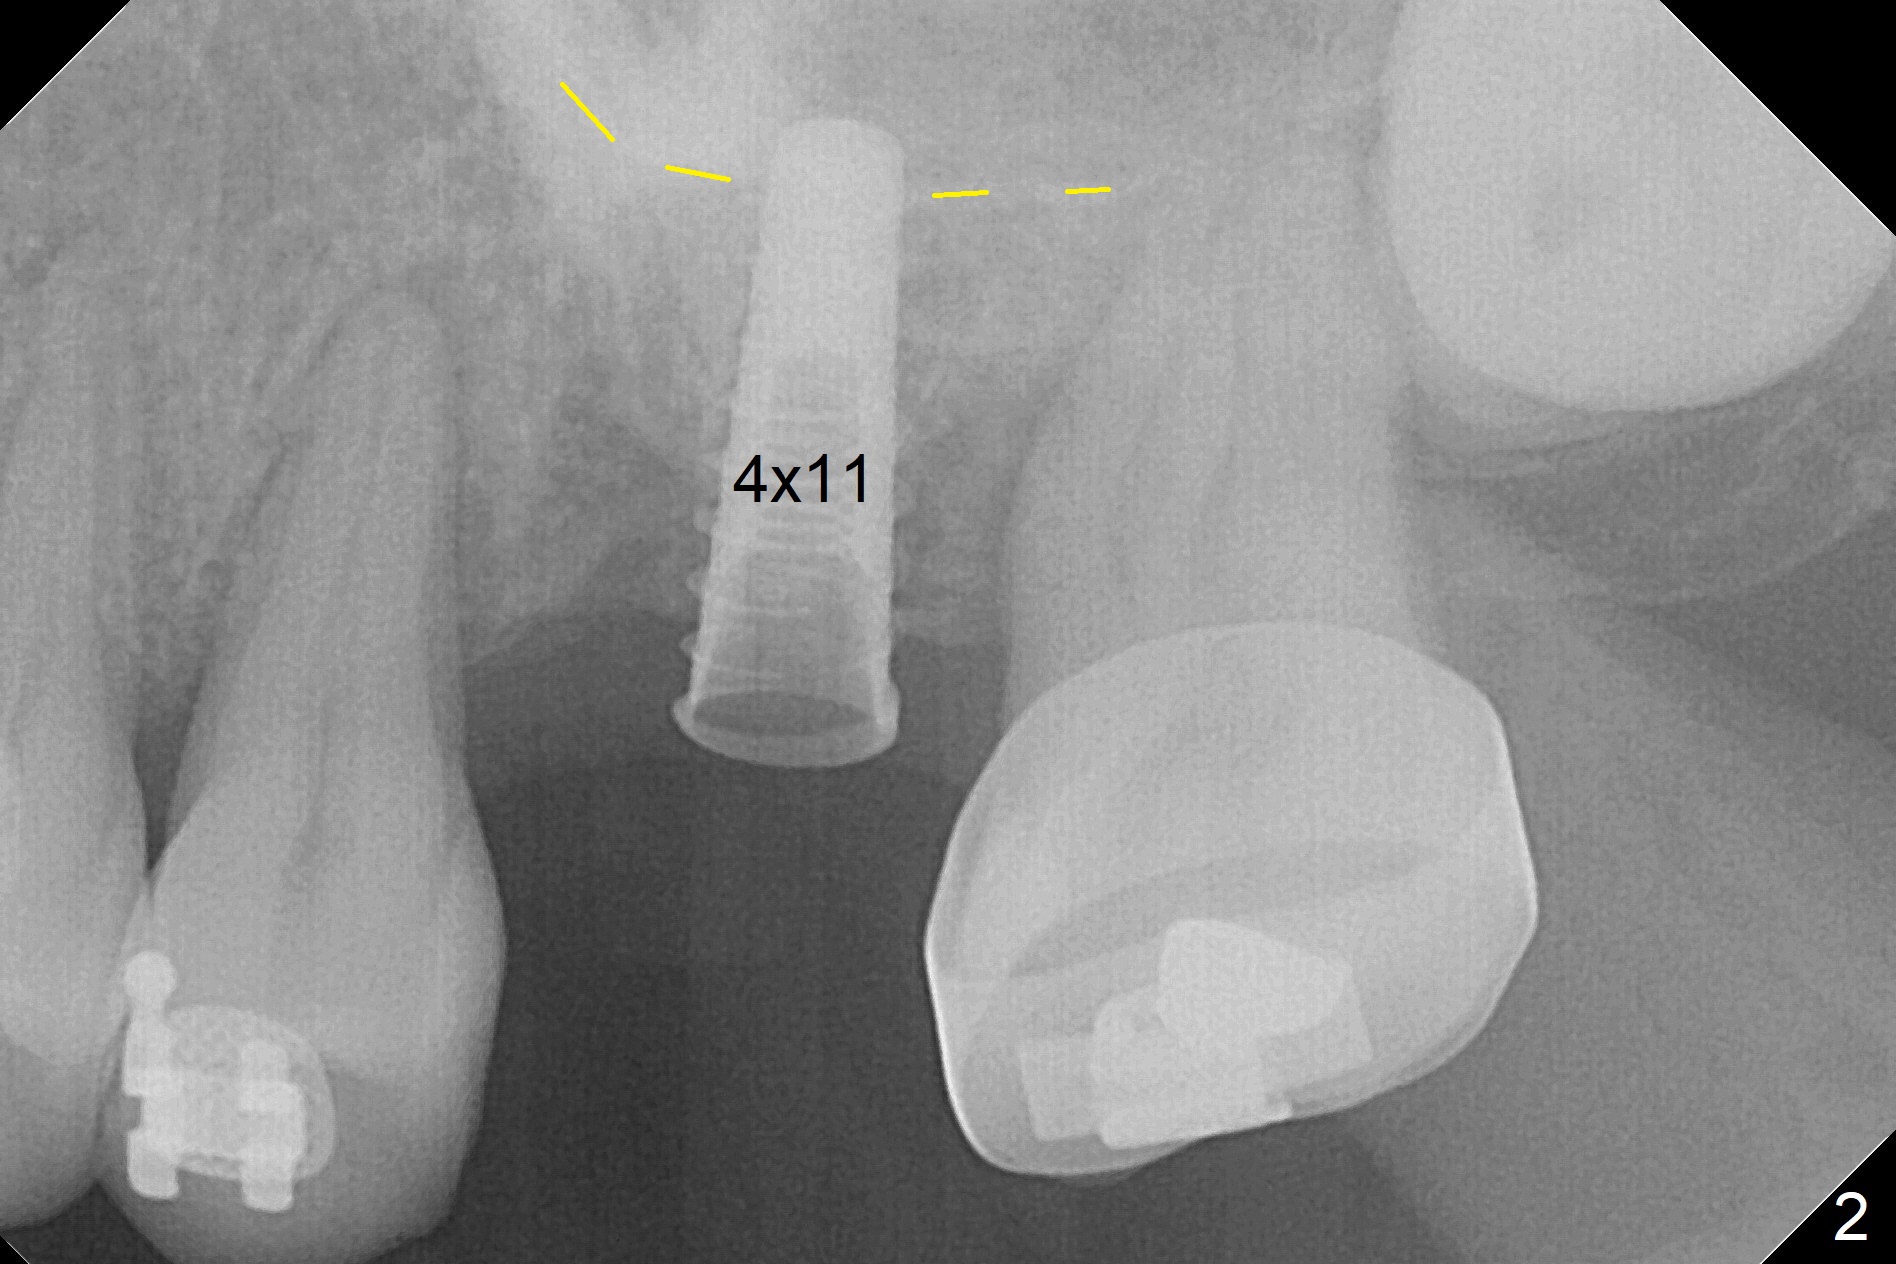

Preop exam shows the narrow ridge at #14. Magic split is used for access and initiation of osteotomy and bone expansion, followed by 3 mm Magic Expander for 11 mm (ME, Fig.1 (yellow line: sinus floor)). In fact the bone is soft. After use of 3.8 mm ME and Lindamann bur (to move the osteotomy distobuccally), a 4x11 mm dummy implant is placed with 20 Ncm (Fig.2). Following use of Lindamann bur for the same purpose as mentioned above, a 4.5x9 mm IBS implant is placed 3 mm subgingival with <30 Ncm (Fig.3,4). Bone graft is placed for sinus lift prior to implantation. A 5x3 mm healing abutment is placed. Bone loss is minimal 3.5 months postop (Fig.5) and striking 8 months postop (after crown cementation, Fig.6-8). The bone loss persists in spite of crown and abutment removal (Fig.9,10). Bone graft or implant redo is planned.